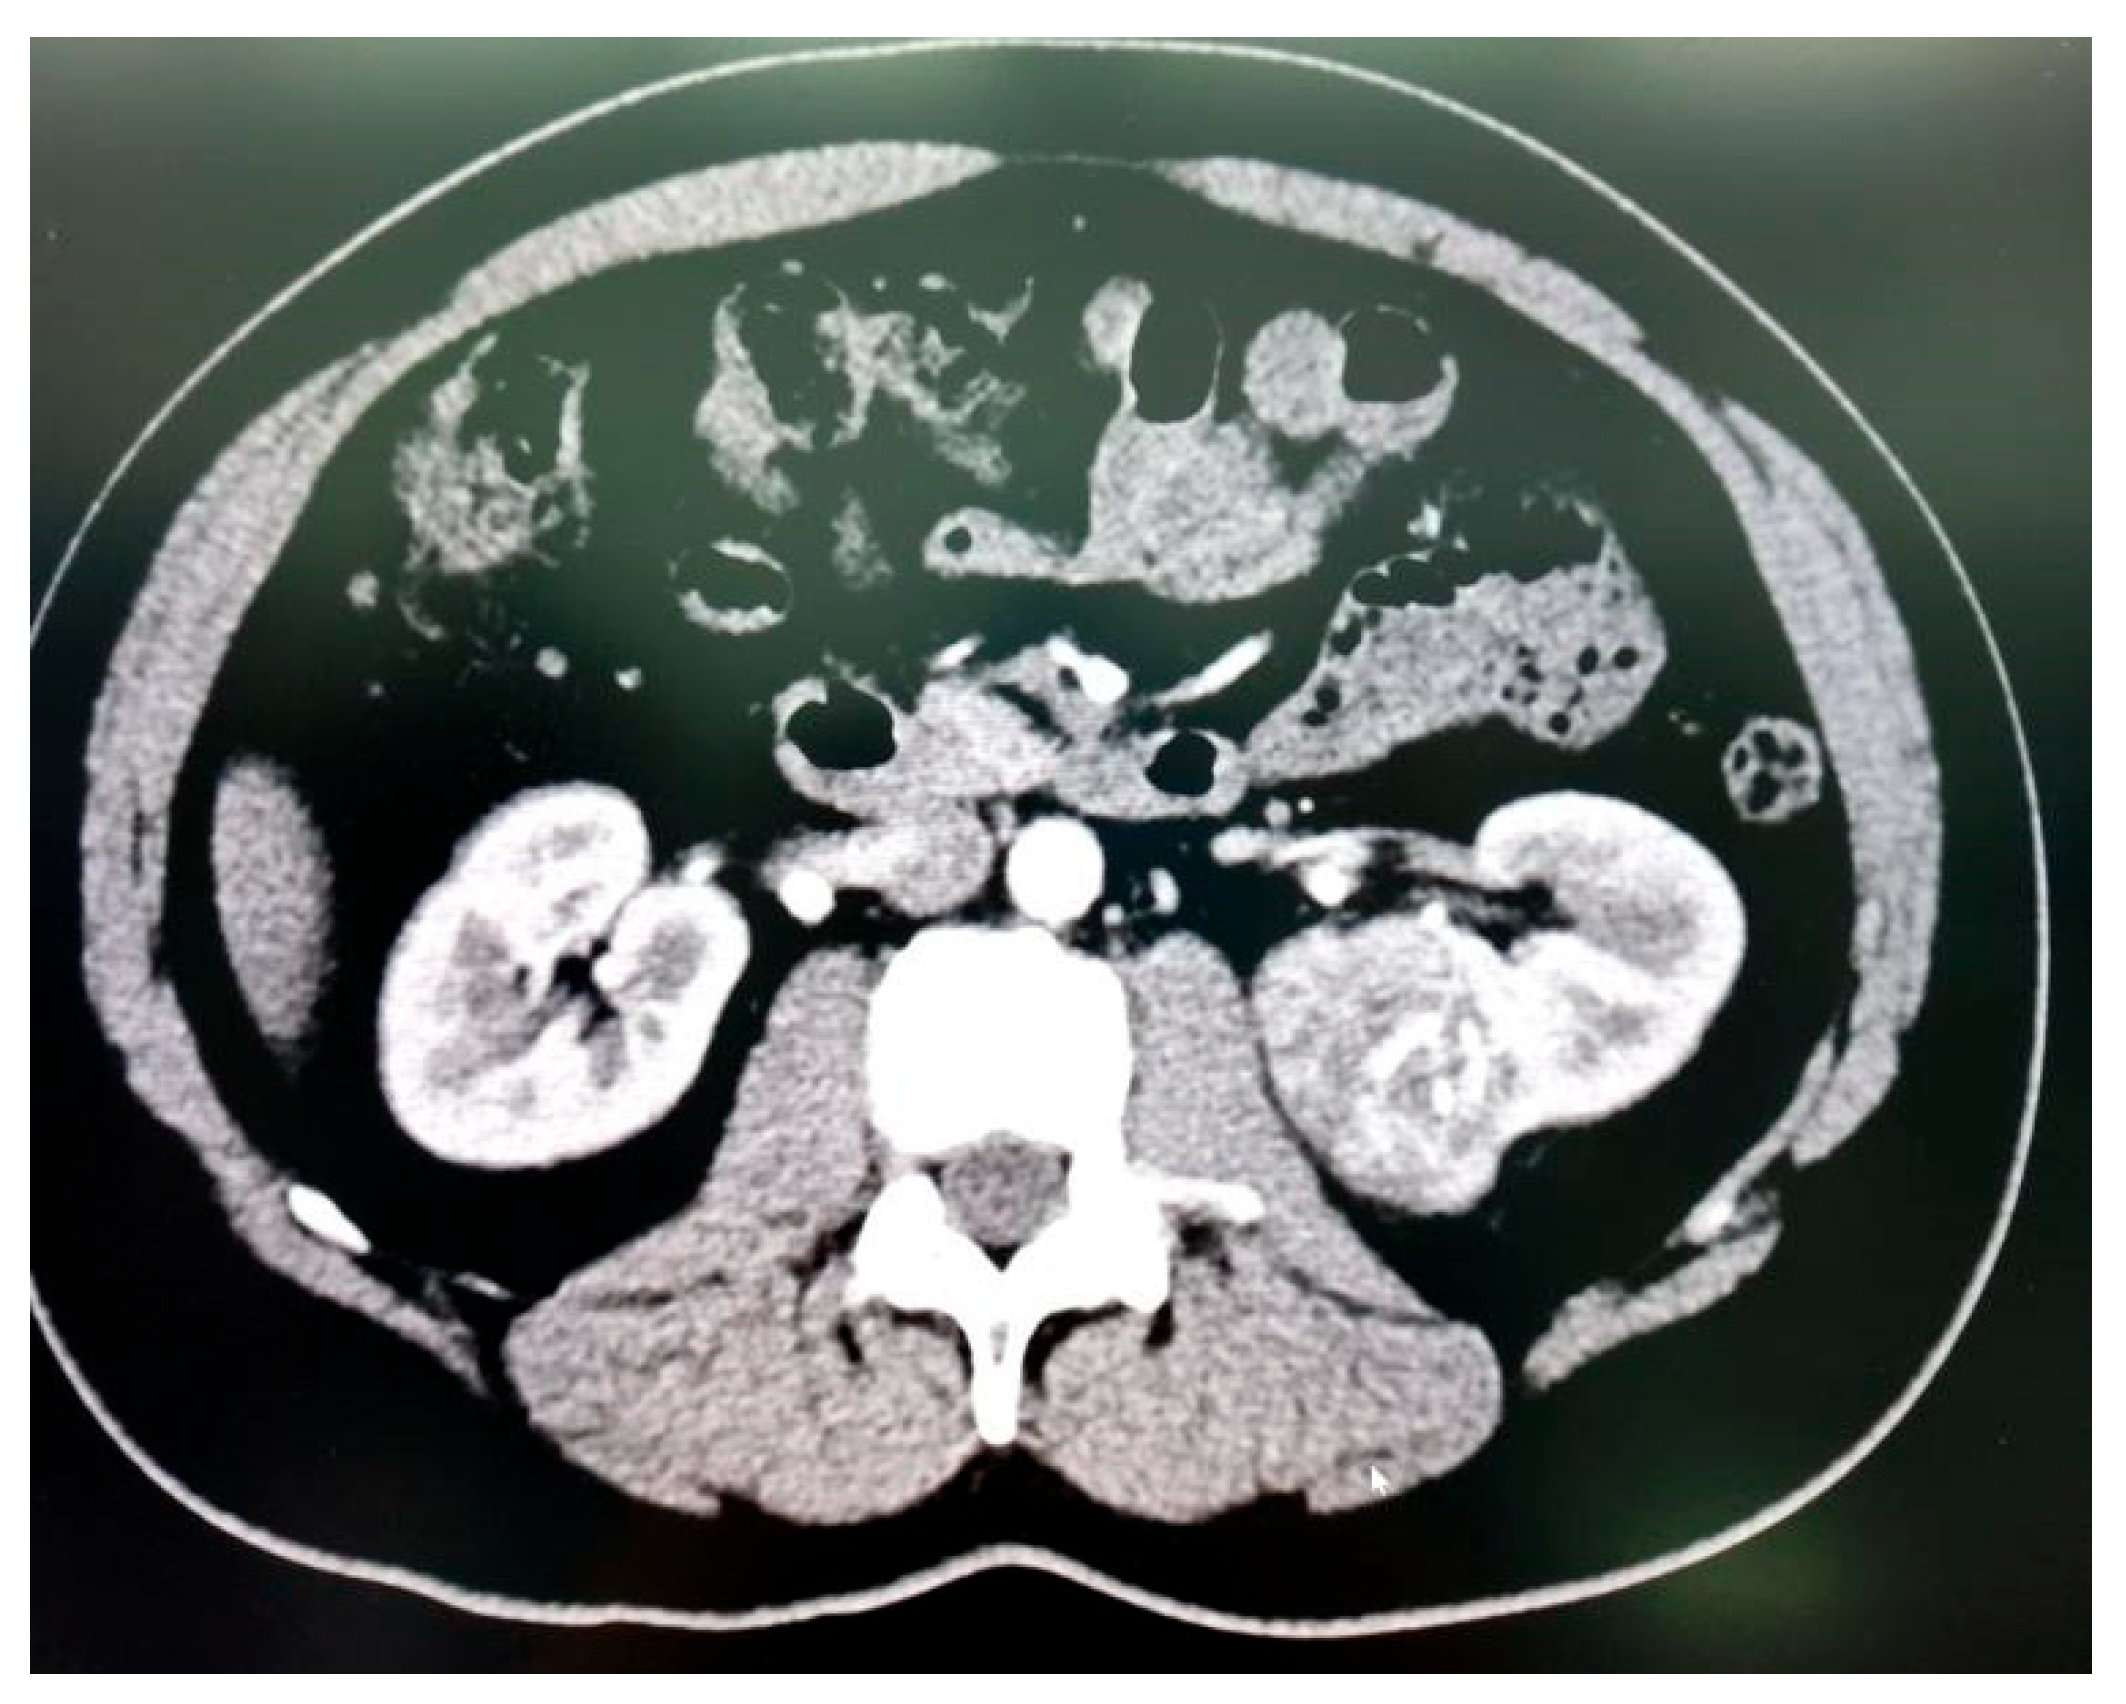

A total of 35 patients, comprising 21 males and 14 females with a mean age of 53.37 ± 15.52 years, underwent RAPN during the study period (Table 1). Tumour characteristics are summarized in Table 2, and perioperative outcomes are detailed in Table 3 and Table 4. All patients had high-complexity tumours, with a median RENAL nephrometry score of 10 (Figure 3A, Figure 3B and Figure 3C).

Figure 3A. Nephrometry score of 10a was given based on the following criteria (R)adius (2 point); (E)xophytic < 50% (2 points); (N)earness < 4mm (3 points); (A)nterior; and (L)ocation relative to polar lines (3 points).

Figure 3B. Nephrometry score of 9p was given based on the following criteria (R)adius (1 point); (E)xophytic < 50% (2 points); (N)earness < 4mm (3 points); (P)posterior; and (L)ocation relative to polar lines (3 points)

Figure 3C. Nephrometry score of 10x was given based on the following criteria (R)adius (1 point); (E)ndophytic entirely (3 points); (N)earness < 4mm (3 points); (X)central; and (L)ocation relative to axial line (3 points)